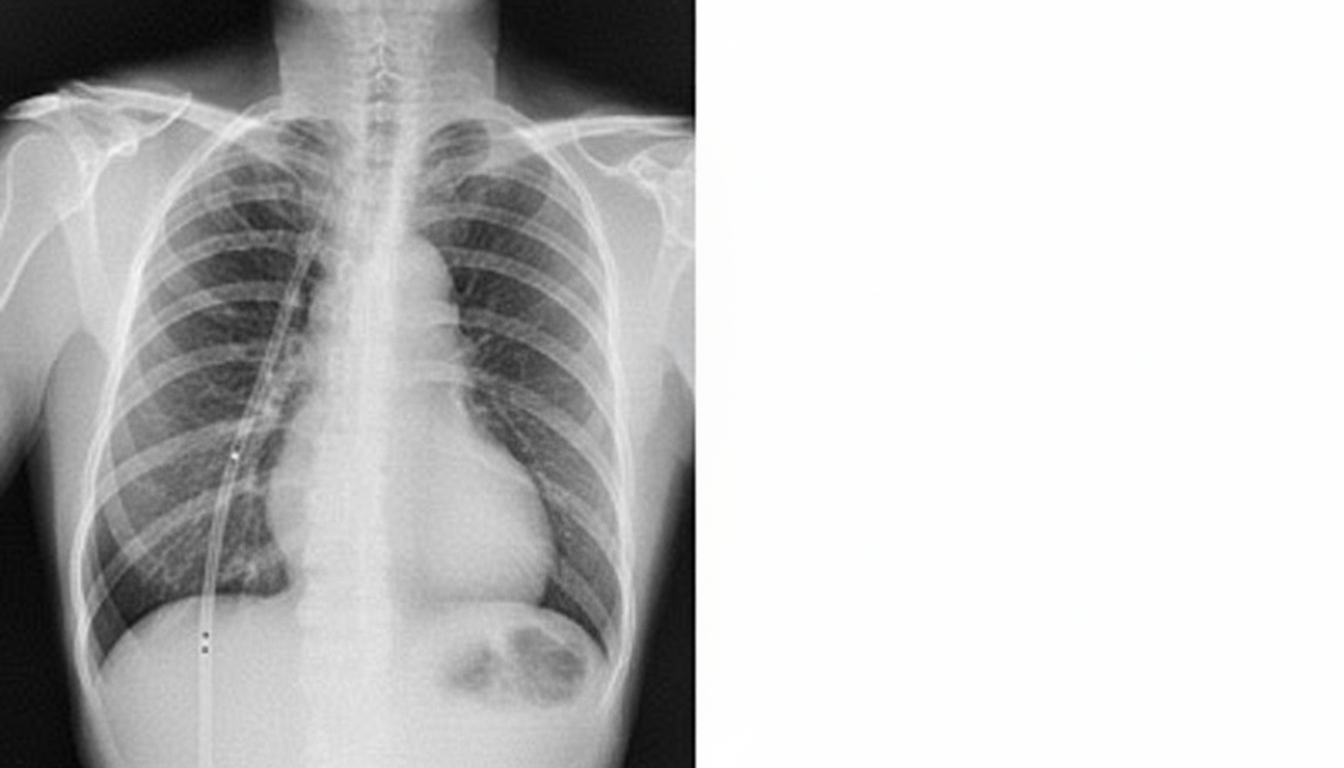

A 53-year-old female nonsmoker is being evaluated with symptoms of progressive shortness of breath. She has a past history of trauma to the right side of the chest. There is no history of asthma, sputum production, or recent chest pain. Chest X-ray is shown. What is the likely diagnosis?

Explanation: ***Organized hemothorax*** - **Post-traumatic history** of right chest trauma combined with **progressive dyspnea** and **pleural thickening** on chest X-ray strongly suggests organized hemothorax (fibrothorax). - Blood collection in the pleural space after trauma can organize into **fibrous tissue**, causing **pleural restriction** and progressive respiratory symptoms. *Calcified cyst* - Would typically appear as a **well-defined, round lesion** with **rim calcification** on chest X-ray, not diffuse pleural thickening. - **No association** with chest trauma history and would not cause progressive dyspnea through pleural restriction. *Blastomycosis* - A **fungal infection** that typically presents with **pulmonary nodules** or **mass-like lesions**, not pleural thickening. - Would be associated with **systemic symptoms** like fever, weight loss, and **productive cough**, which are absent in this case. *Asbestosis* - Requires **occupational exposure** to asbestos fibers, typically in construction or shipyard workers. - Presents with **bilateral lower lobe fibrosis** and **pleural plaques**, not unilateral right-sided pleural thickening following trauma.